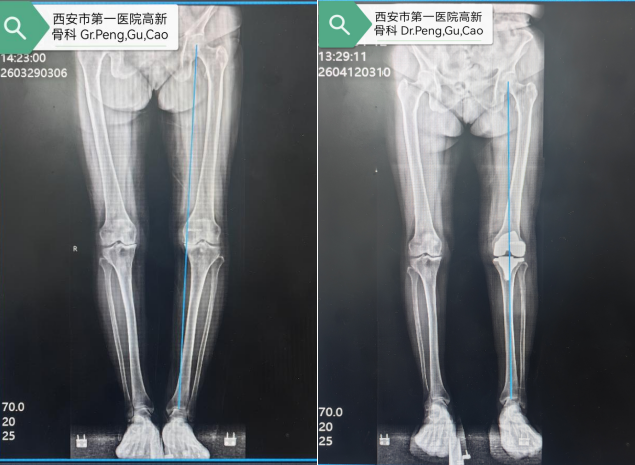

骨科顾始伟副主任医师考虑到患者基础疾病多、手术风险高,立即与关节专家彭主任组织心血管内科、内分泌科、麻醉科等多学科专家会诊,制定个性化术前方案,并精准测算截骨角度与假体大小,制定“毫米级”手术方案。手术当天,在麻醉科、手术室密切配合下,彭主任主刀,手术历时不到1小时,出血量远低于预期,未出现术中并发症。

术后,团队采用“循序渐进、个性化康复”原则,从踝泵运动到关节屈伸、行走训练全程跟踪指导。目前胡阿姨膝关节疼痛完全缓解,腿型从“O”型变笔直,已能自主行走。